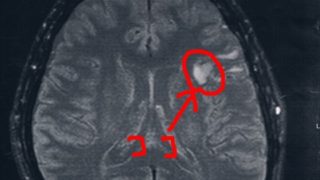

GLIOMA:手術後44ヶ月目の検査

半年前(2018/3/8)の検査の記録。ブログに追加するのを忘れていたらしい。2014/6/23の覚醒手術から約44か月になる。MRI検査の結果、半年前と比べても変化は無し!今回2018/3/8(手術後44か月)のMRI画像前回2017/9...